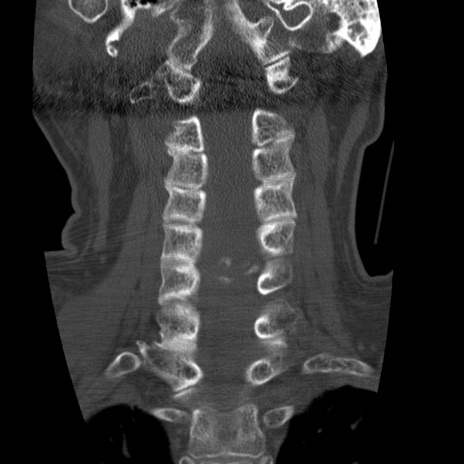

症例50 頚椎CT(冠状断像)

頚椎CT